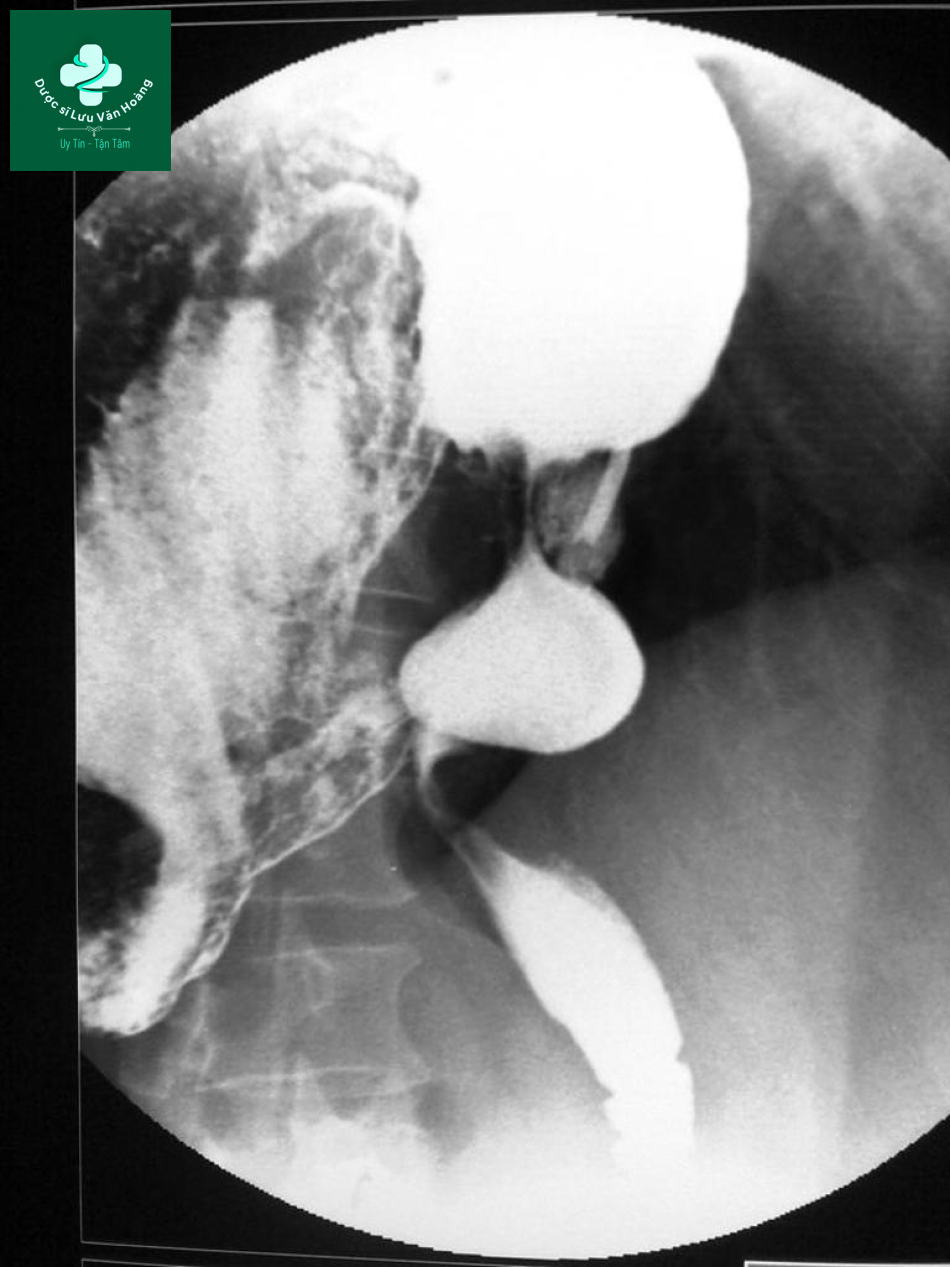

- Case 3: dấu hiệu đồng hồ cát trên phim chụp có uống barit.